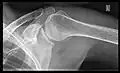

- Y-projection

The lateral contour of the shoulder should be positioned in front of the film in a way that the longitudinal axis of the scapula continues parallel to the path of the rays. This method reveals:[26]

- The horizontal centralization of the humerus head and socket

- The osseous margins of the coraco-acromial arch and hence the supraspinatus outlet canal

- The shape of the acromion

This projection has a low tolerance for errors and, accordingly, needs proper execution.[26] The Y-projection can be traced back to Wijnblath’s 1933 published cavitas-en-face projection.[27]

Y-projection conventional radiography